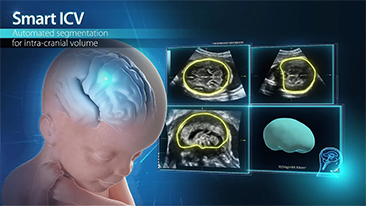

System Nuewa zosta? stworzony specjalnie na potrzeby zdrowia kobiet w okresie przed ci???, w trakcie ci??y i po?ogu. Oparty na zaawansowanej platformie ZST+ oferuje pe?n? gam? inteligentnych rozwi?zań i pozwala na wszechstronn? oraz efektywn? diagnostyk?, wspieraj?c codzienne wyzwania kliniczne.

Technologia